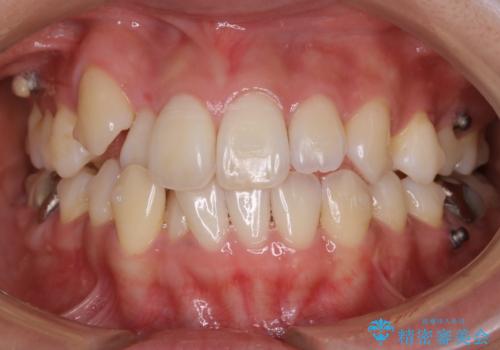

【非抜歯】インビザライン 隠れた前歯を並べる矯正治療

- 前歯のガタつき・奥に隠れてしまっている歯の矯正治療を希望されて初診来院されました。

顔貌的に口元を下げたいといった希望はなく抜歯はなるべく避けたいとのご要望からマウスピース装置(インビザライン)での治療を行うこととなりました。